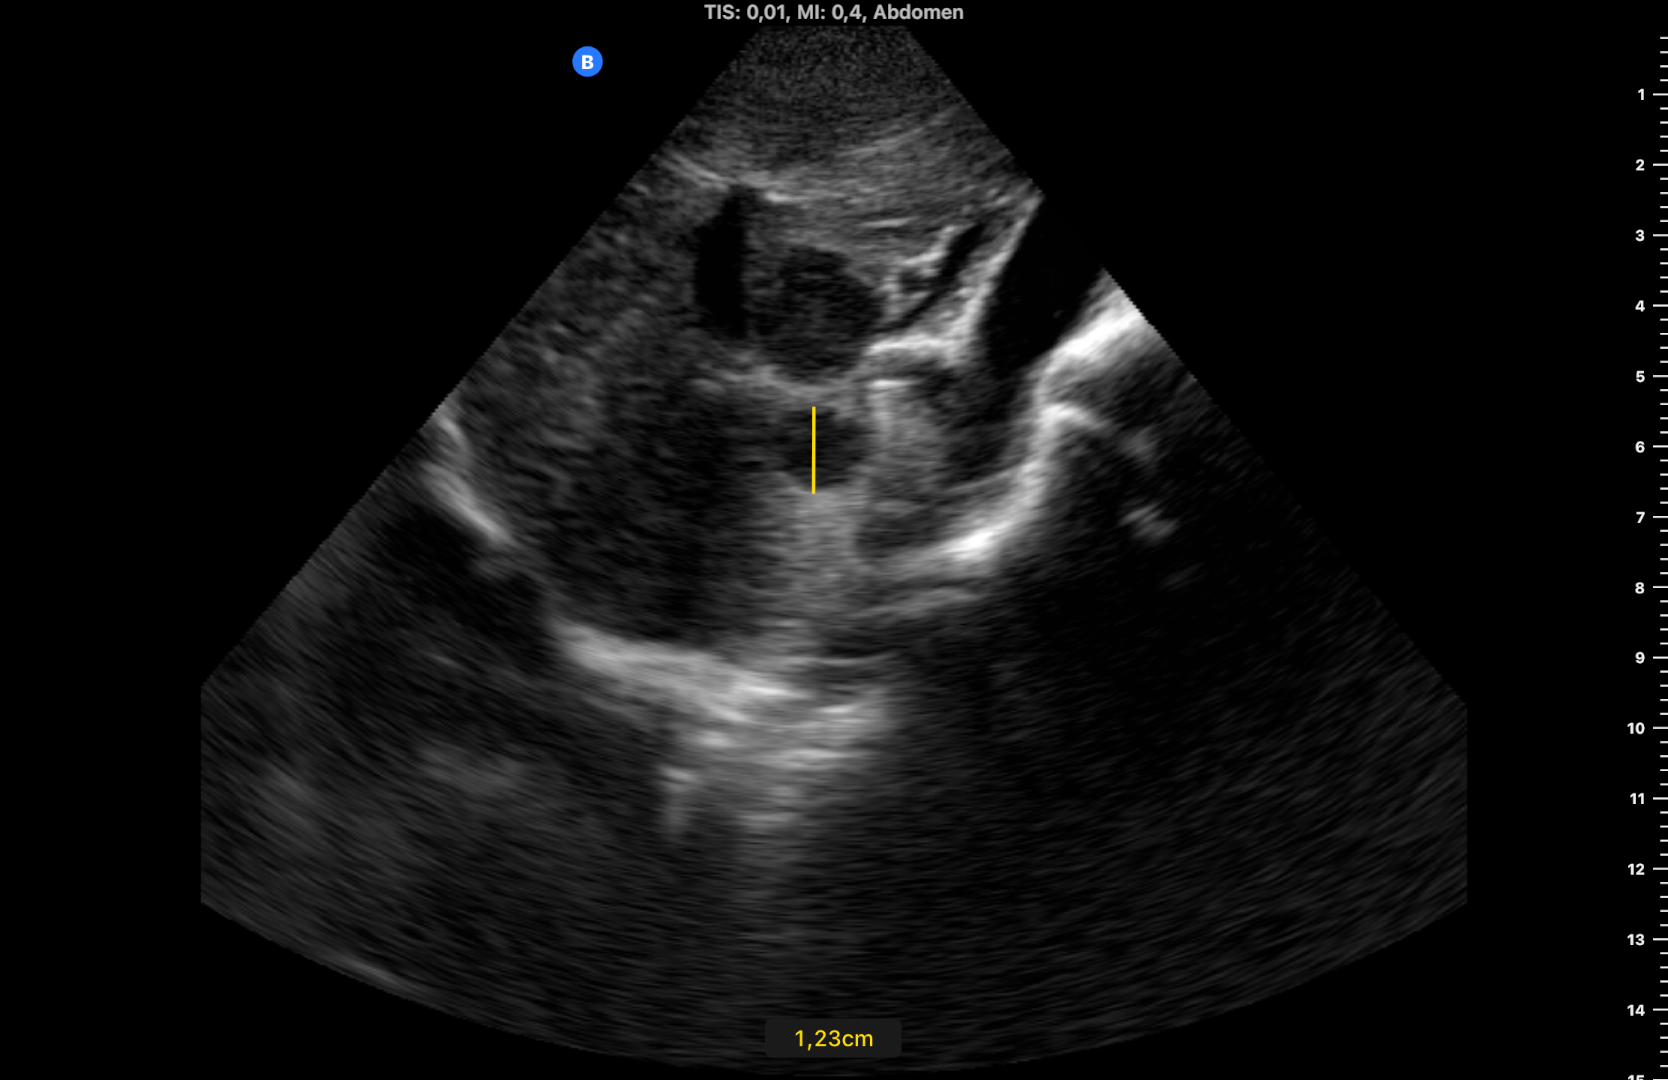

Se observan dos imágenes hipoecogénicas en el parénquima hepático, bien delimitadas, con alguna lobulación a nivel de segmento 3 y en lóbulo caudado de 2,5 y 1,2 cm de diámetro (figuras 1 y 2) y una porta de 13,1 mm de calibre. Se confirman los hallazgos con ecógrafo de consola (figura 3) (vídeos disponibles).

Seis meses después, al revisar la historia su médico advierte que el paciente olvidó su cita y vuelve a derivarlo tras realizar otra ecografía clínica, observando las mismas lesiones sin cambios (figura 4), lo que sugería benignidad. Finalmente se realiza TC: «lesión hipodensa de apariencia sólida en lóbulo caudado de 14 mm y lesión subcapsular de 9 mm en segmento VIII» y RM: «múltiples lesiones hepáticas benignas, la mayoría corresponden a angiomas hepáticos (los de mayor tamaño se localizan en los segmentos 1 y 3), otras se corresponden a pequeños quistes biliares subcentimétricos».